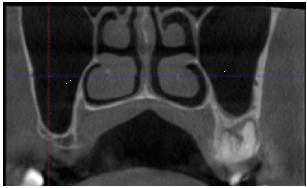

El suministro de sangre al seno maxilar, está proporcionado por 4 ramas principales: la arteria alveolar superior posterior, la arteria infraorbitaria, la arteria palatina descendente y la arteria esfenopalatina. El abordaje de la técnica de ventana lateral, es la que presenta mayor riesgo en dañar los vasos sanguíneos en esa área, especialmente la arteria ASP. (Fig. 1) La posibilidad y el grado de severidad de la hemorragia dependen del diámetro de la arteria (29,30,31). Por lo tanto, es de suma importancia realizar un adecuado estudio pre quirúrgico del área, usando técnicas avanzadas, como el uso de la tomografía computarizada (CBCT). (Fig. 2) El uso de las CBCTs, ha demostrado ser una herramienta indispensable para el diagnóstico e identificación de estructuras anatómicas para una correcta elección de abordaje quirúrgico, en especial cuando la arteria ASP es mayor a 0.5 mm (32,33). Varios factores y variables de pacientes, como edad, género, estado de dentición, volumen de seno, altura y ancho pueden influenciar en la localización de la arteria.